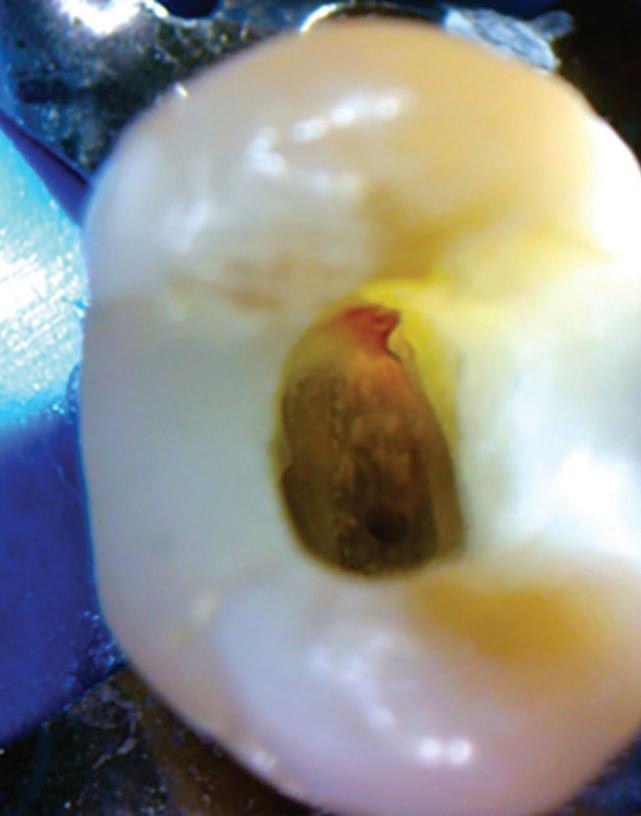

Fig. 19-1. Paciente idoso submetido a tratamento endodôntico (dente 25). (a) Canais atresiados (visualizados na radiografia periapical.) ( bliteração da entrada do canal vestibular. (d) Canal localizado e ampliado (uso de microscopia e ultrassom). ( a